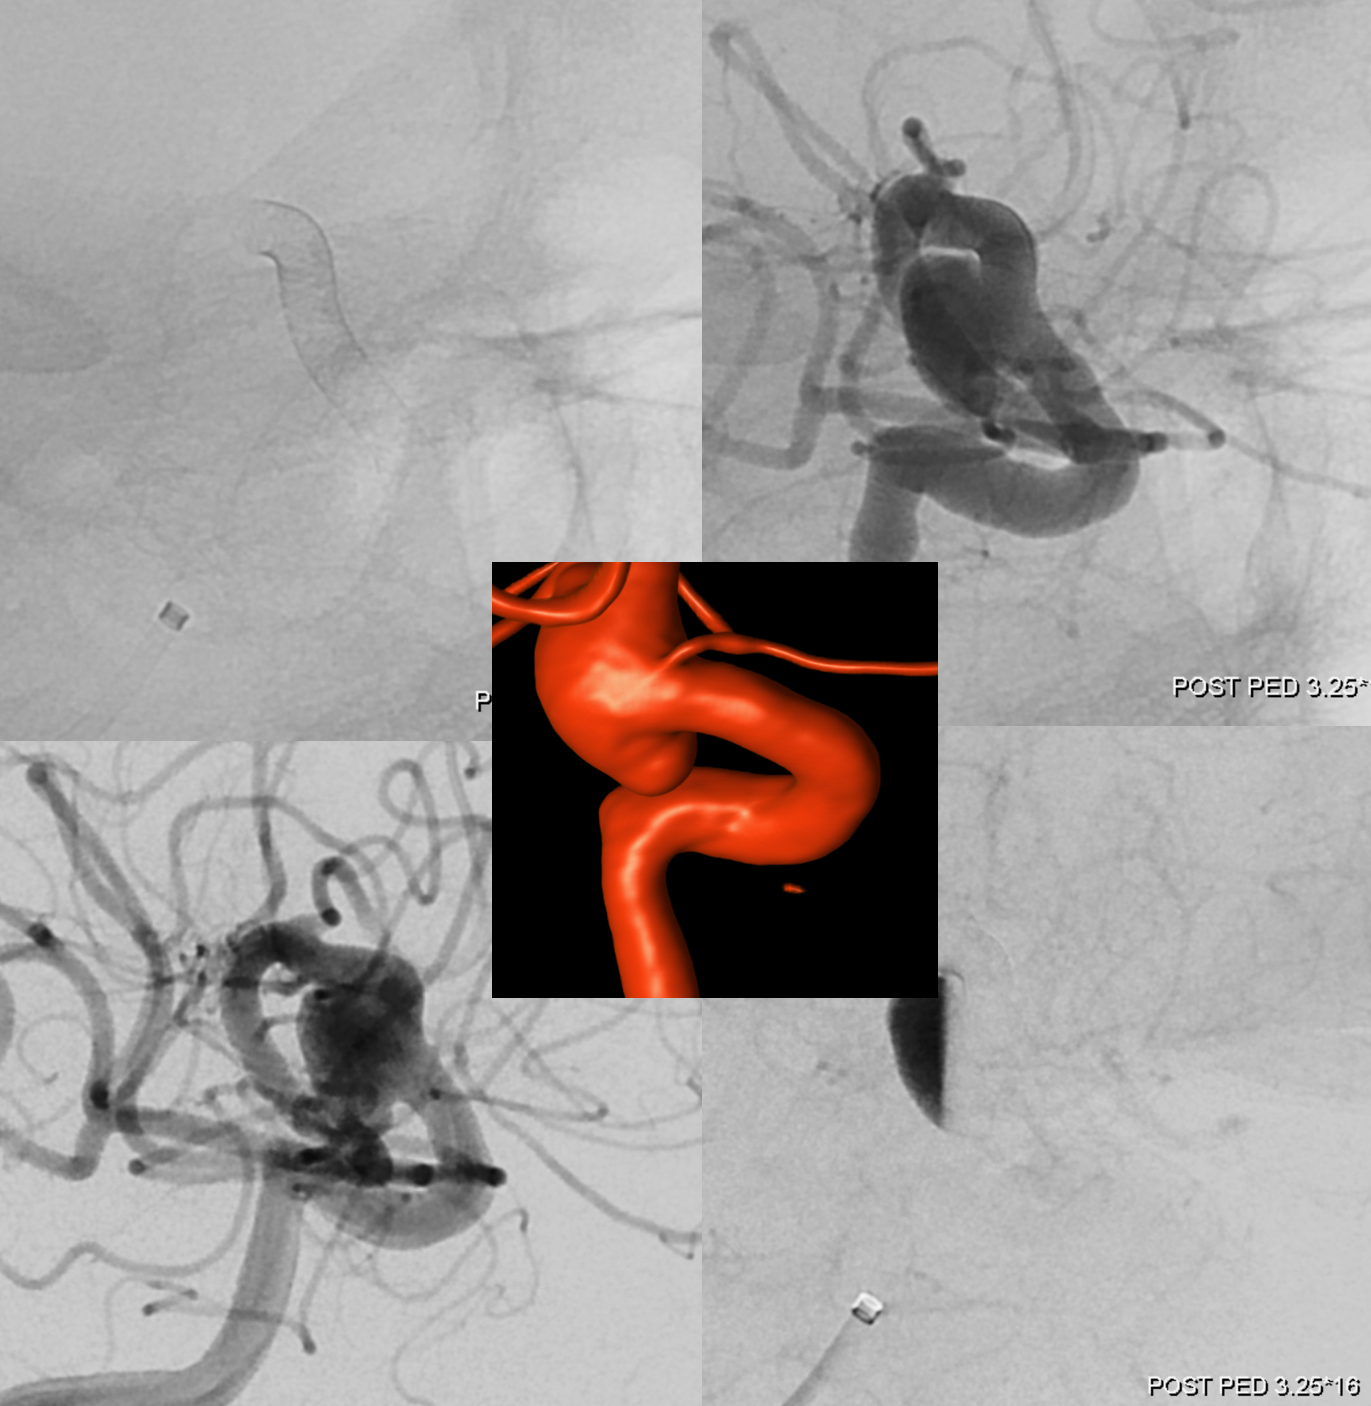

Another interesting topic. Courtesy Eytan Raz MD PhD. Hypophyseal Aneurysm, post PED

Follow up — notice a “lower” origin of the ophthalmic now, and a small vessel (arrow) from the medial wall, adjacent to the new ophthalmic ostium.

What happened to the ophthalmic origin? See Pipeline Device Properties page for more into. Basically, the Pipeline is not fully apposed to the ophthalmic ostium, creating a secondary communication between the aneurysm and the ophthalmic — essentially incorporating the ophthalmic ostium into the aneurysm. As the aneurysm shrinks, the flow to ophthalmic is reorganized. Other examples are on the Pipeline page.

Fine. But what about the little branch — the superior hypophyseal artery?

Whats interesting is that the superior hypophyseal was part of the aneurysm. Now that the aneurysm has shunk its ostium has come to appose the Pipeline, and its flow is preserved. Other interesting things are there too.